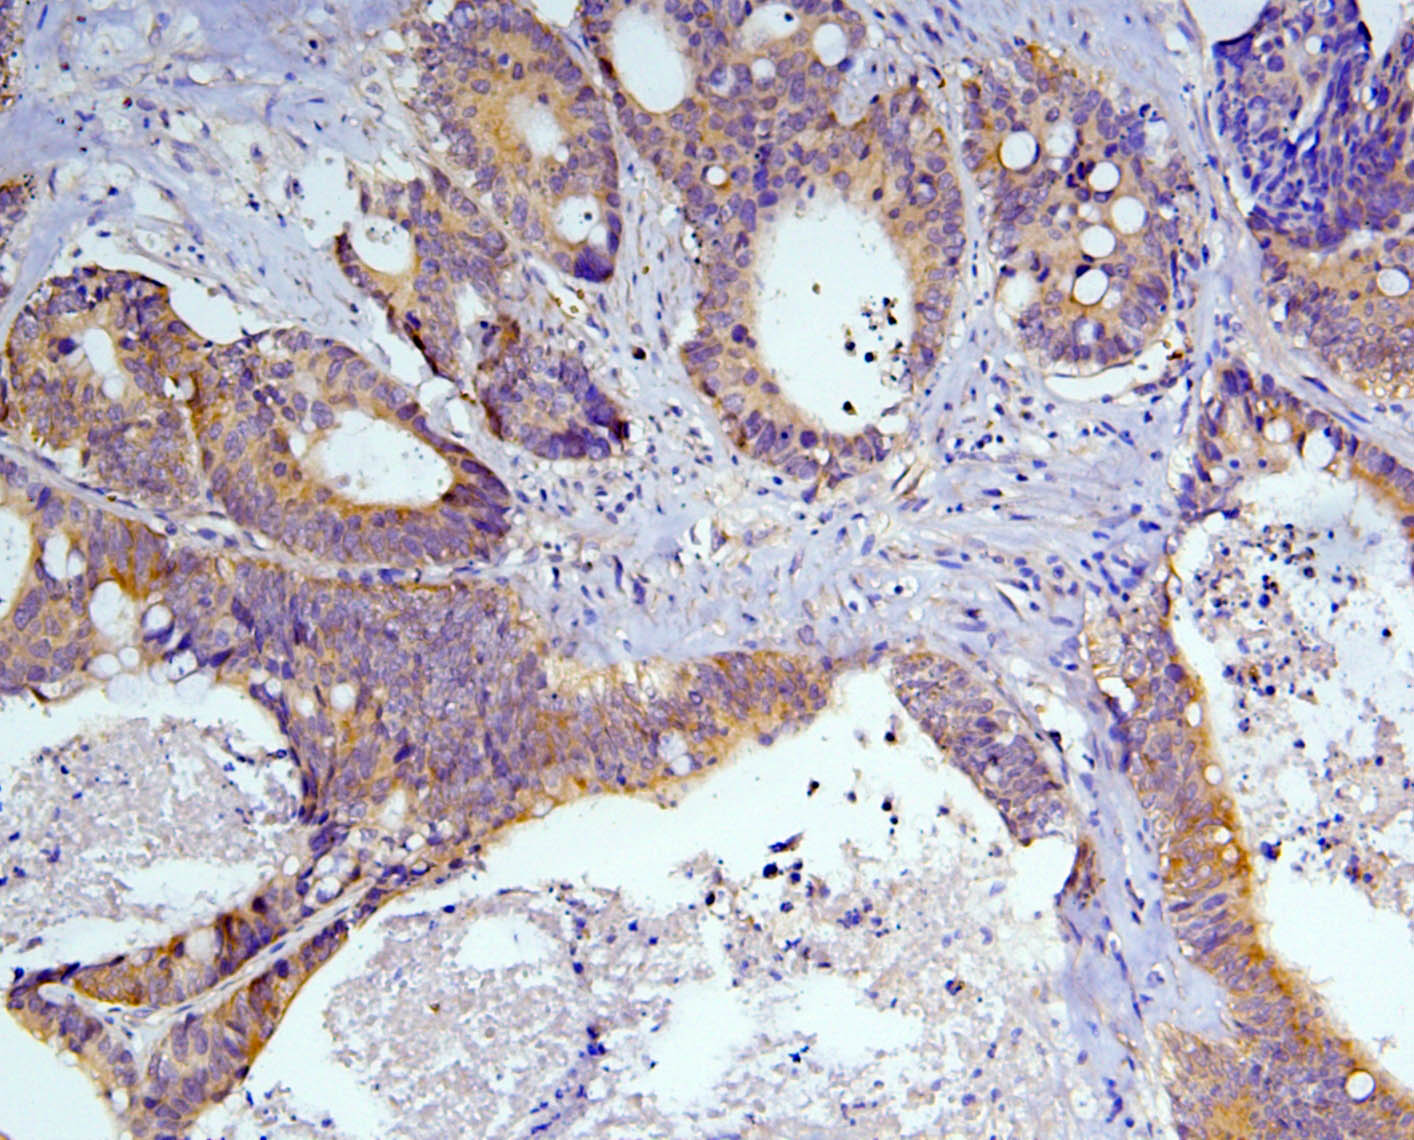

IHC analysis of Caspase 3/CASP3 (p17) using anti-Caspase 3/CASP3 (p17) antibody (M00334-7).

Caspase 3/CASP3 (p17) was detected in a paraffin-embedded section of human intestinal cancer tissue. Biotinylated goat anti-mouse IgG was used as secondary antibody. The tissue section was incubated with mouse anti-Caspase 3/CASP3 (p17) Antibody (M00334-7) at a dilution of 1:200 and developed using Strepavidin-Biotin-Complex (SABC) (Catalog # SA1021) with DAB (Catalog # AR1027) as the chromogen.